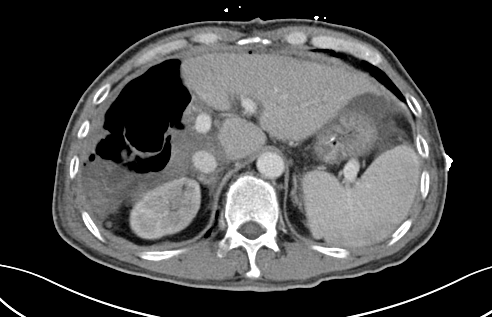

术前CT

近段时间,他因右上腹疼痛就诊于泸州市中医医院,在检查中发现右侧肝脏有一12公分左右的包块,初步考虑为恶性肿瘤,后收治入院。通过全面检查,诊断其为肝癌晚期,并伴有乙型肝炎、肝硬化等病症。

“该患者入院后,通过肝脏CT,我们发现,由于其右肝肿瘤巨大,而正常的左肝体积比较小,手术预切除肝体积达70%以上,术后残肝体积仅28.3%,再加上该患者存在乙肝和肝硬化,剩余肝脏不足以维持他身体正常运转所需,不具备肝脏手术切除的基本要求。”胡伟表示。